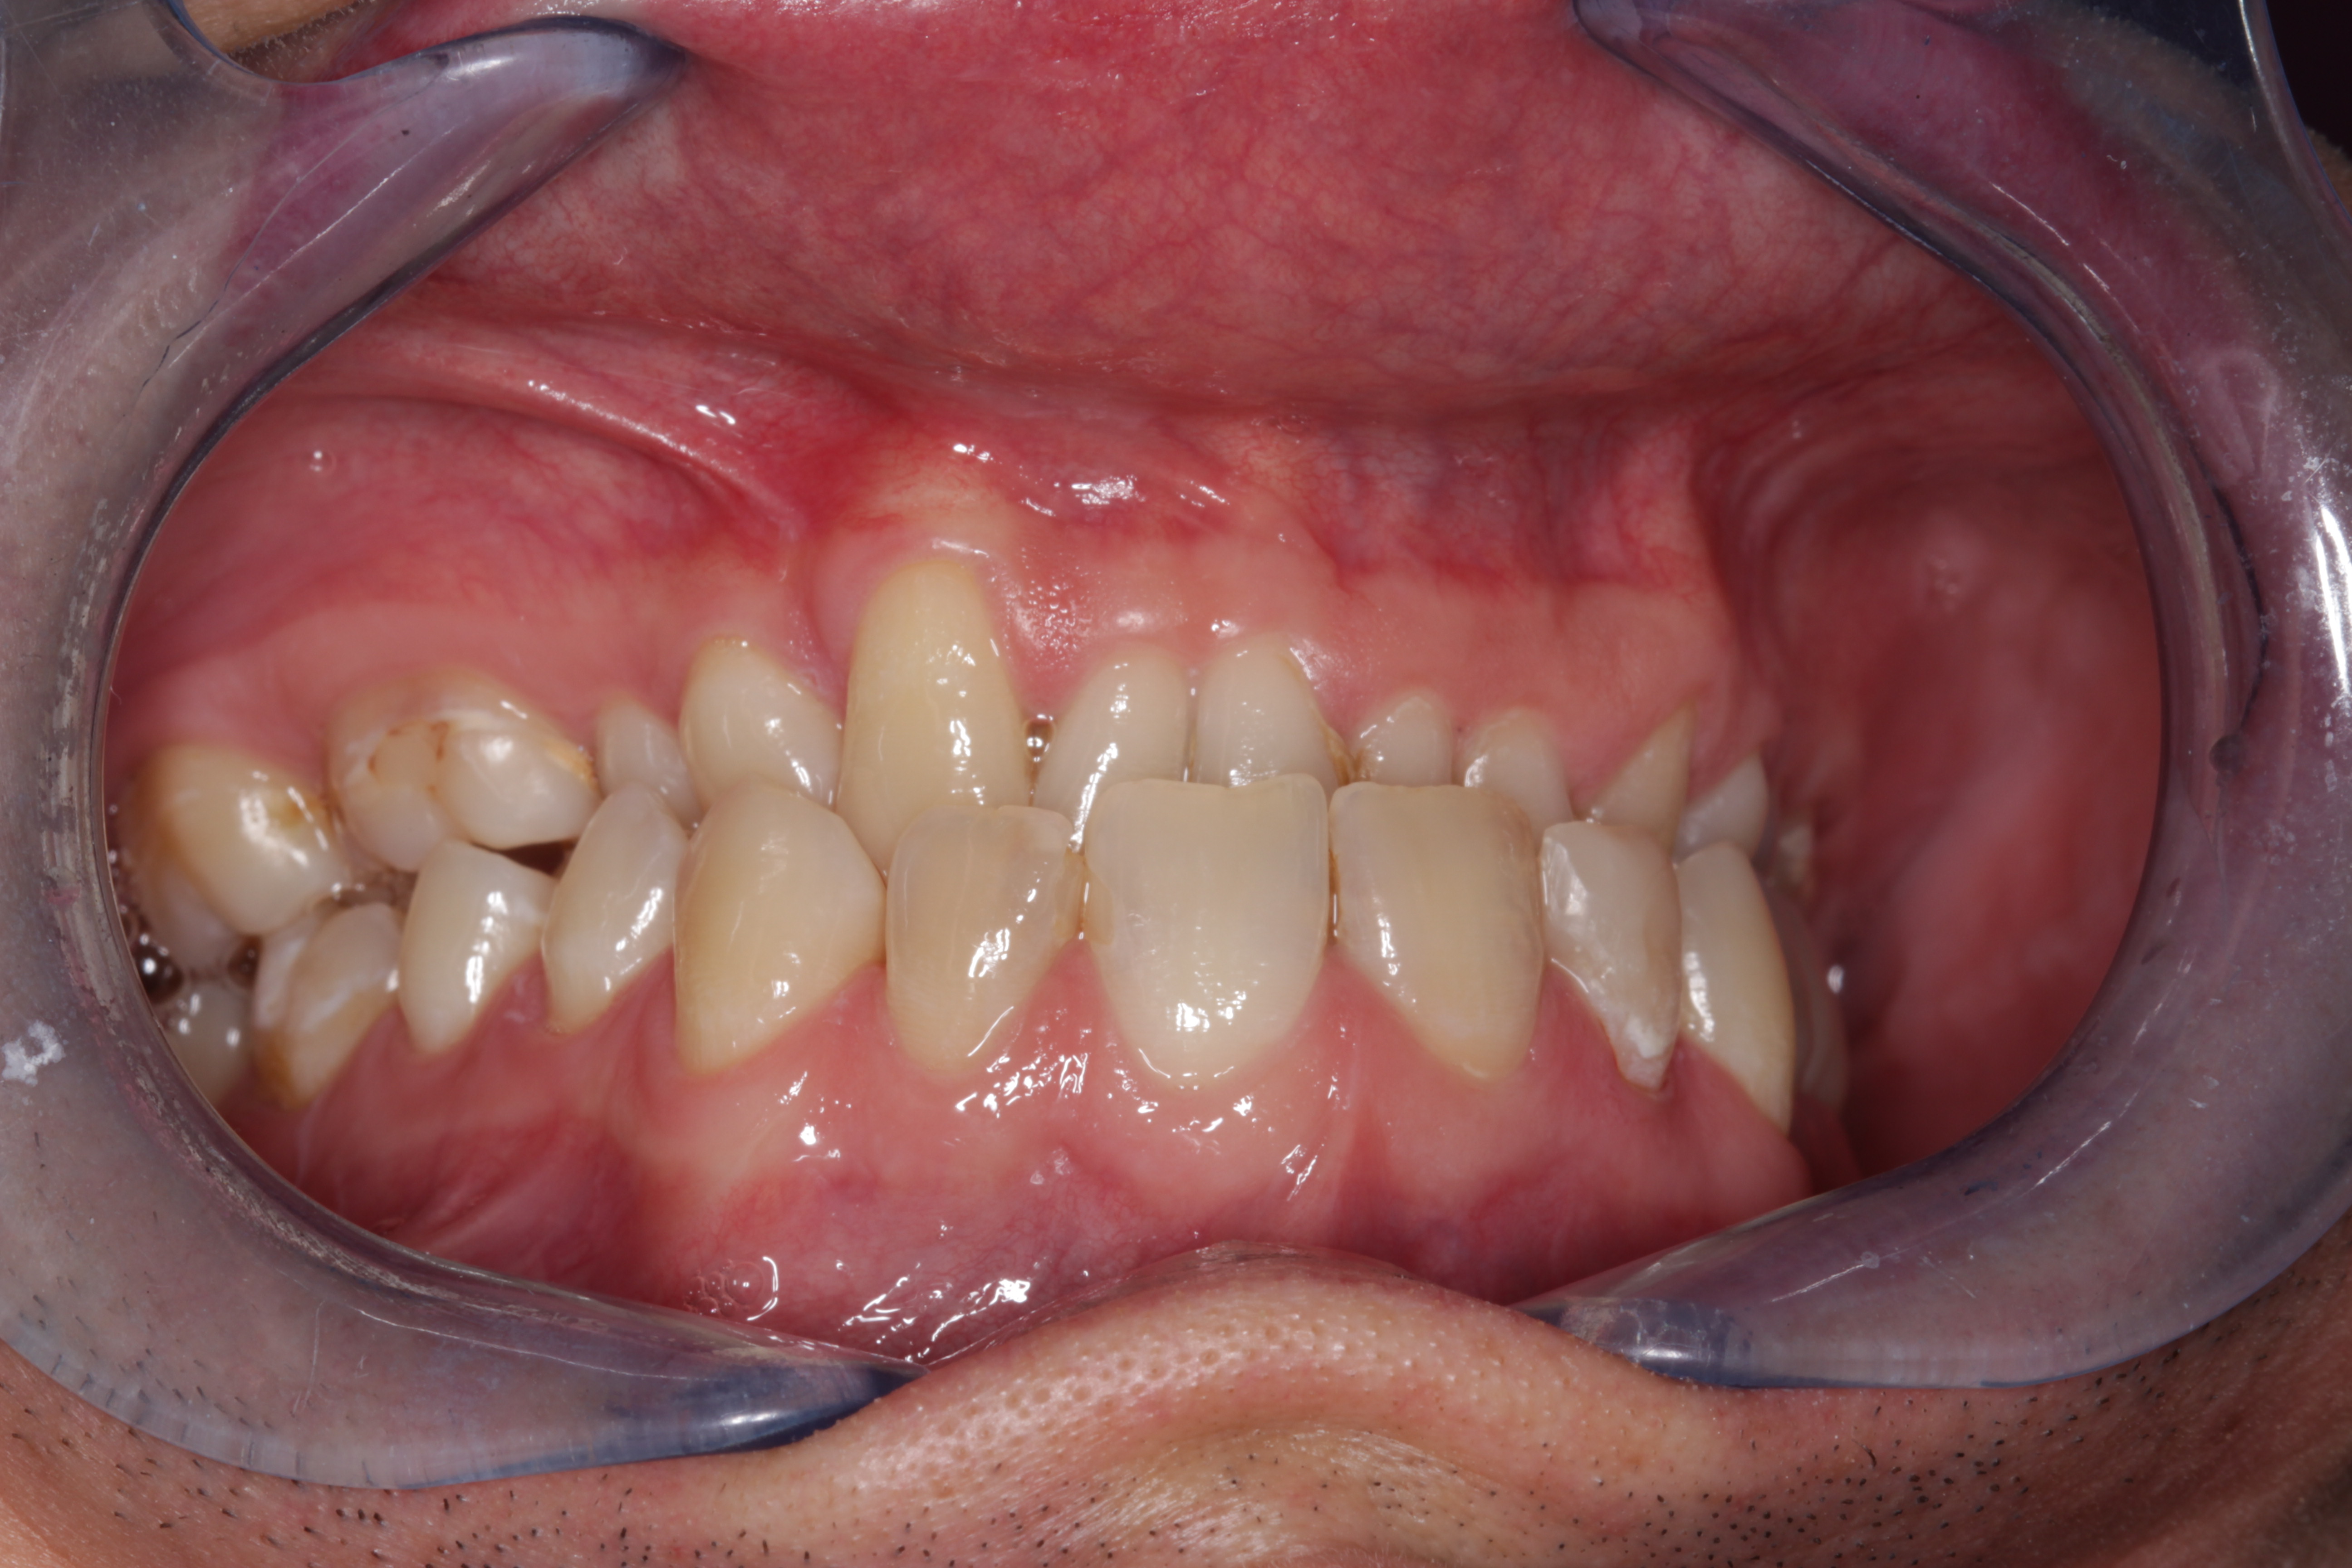

- Rehabilitación postraumática